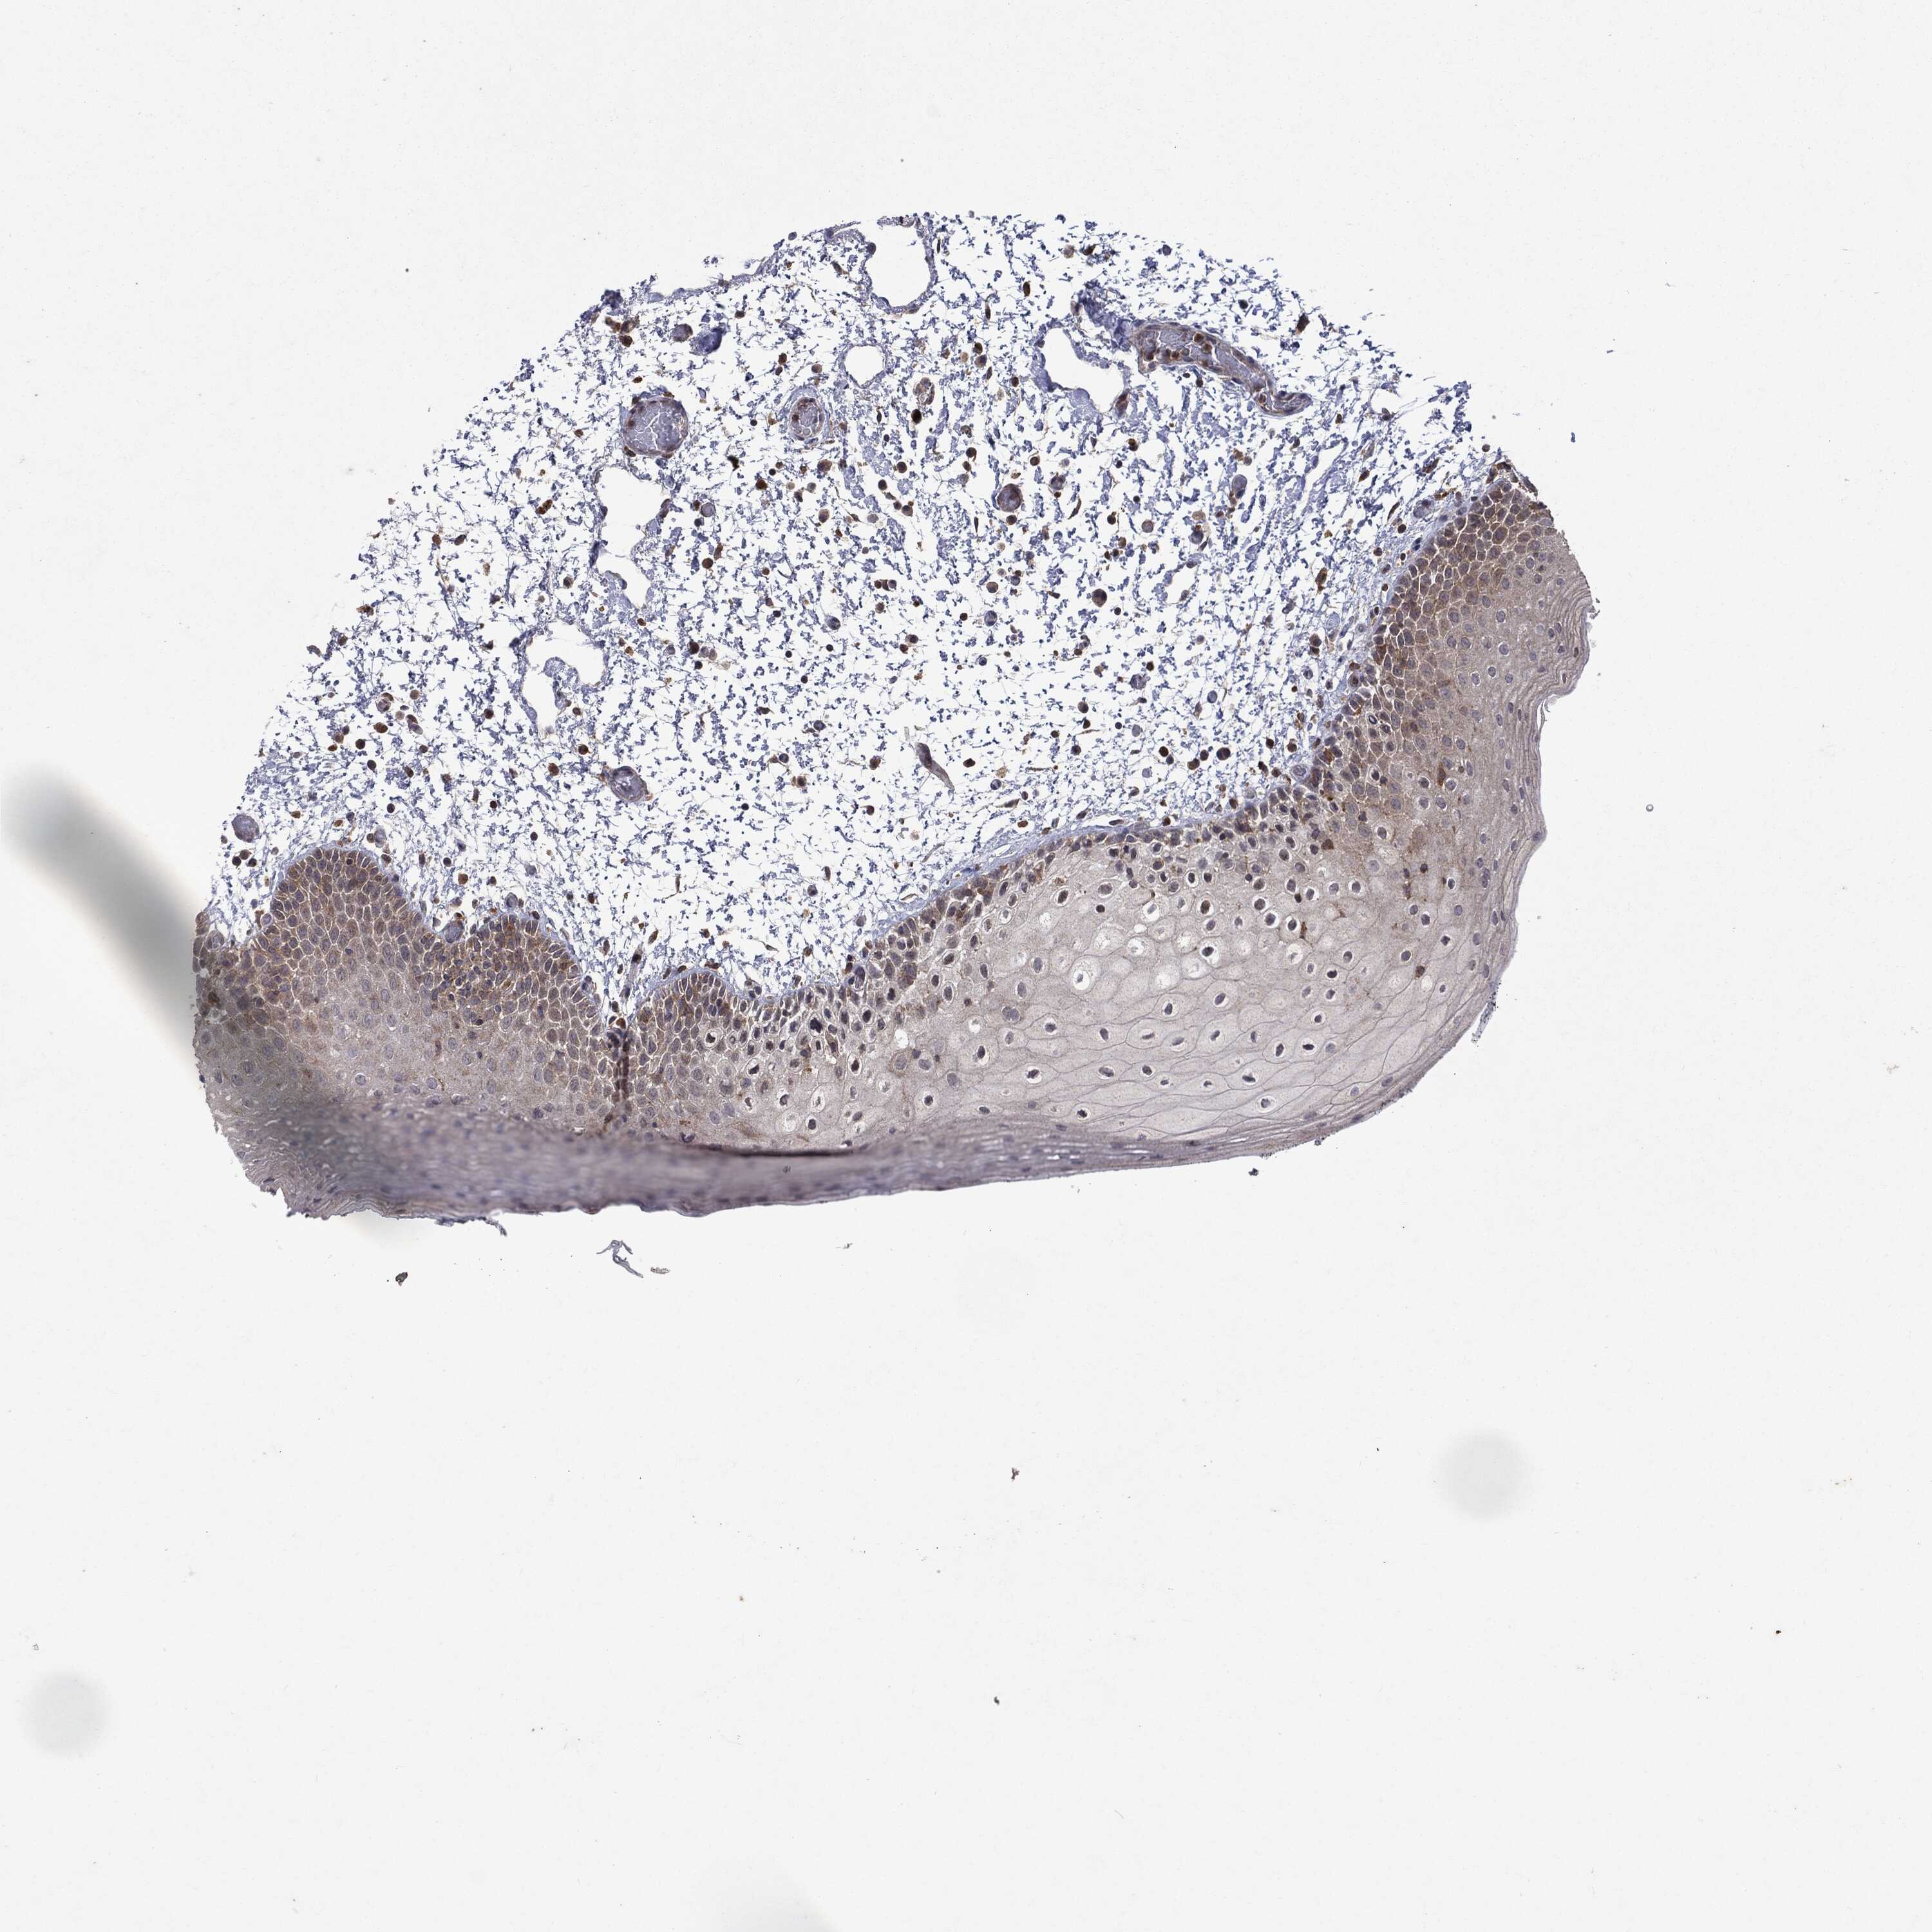

ORAL MUCOSA - Antibody stainingi

Antibody staining in the annotated cell types in the current human tissue is reported as not detected, low, medium, or high, based on conventional immunohistochemistry profiling in selected tissues. This score is based on the combination of the staining intensity and fraction of stained cells.

Each image is clickable and will lead to virtual microscopy that enables deeper exploration of all samples and also displays staining intensity scores, fraction scores and subcellular localization as well as patient and tissue information for each sample.

Antibody HPA031335Antibody CAB004076Antibody CAB080153Antibody CAB080157

Squamous epithelial cells MediumNot detectedNot detectedMedium